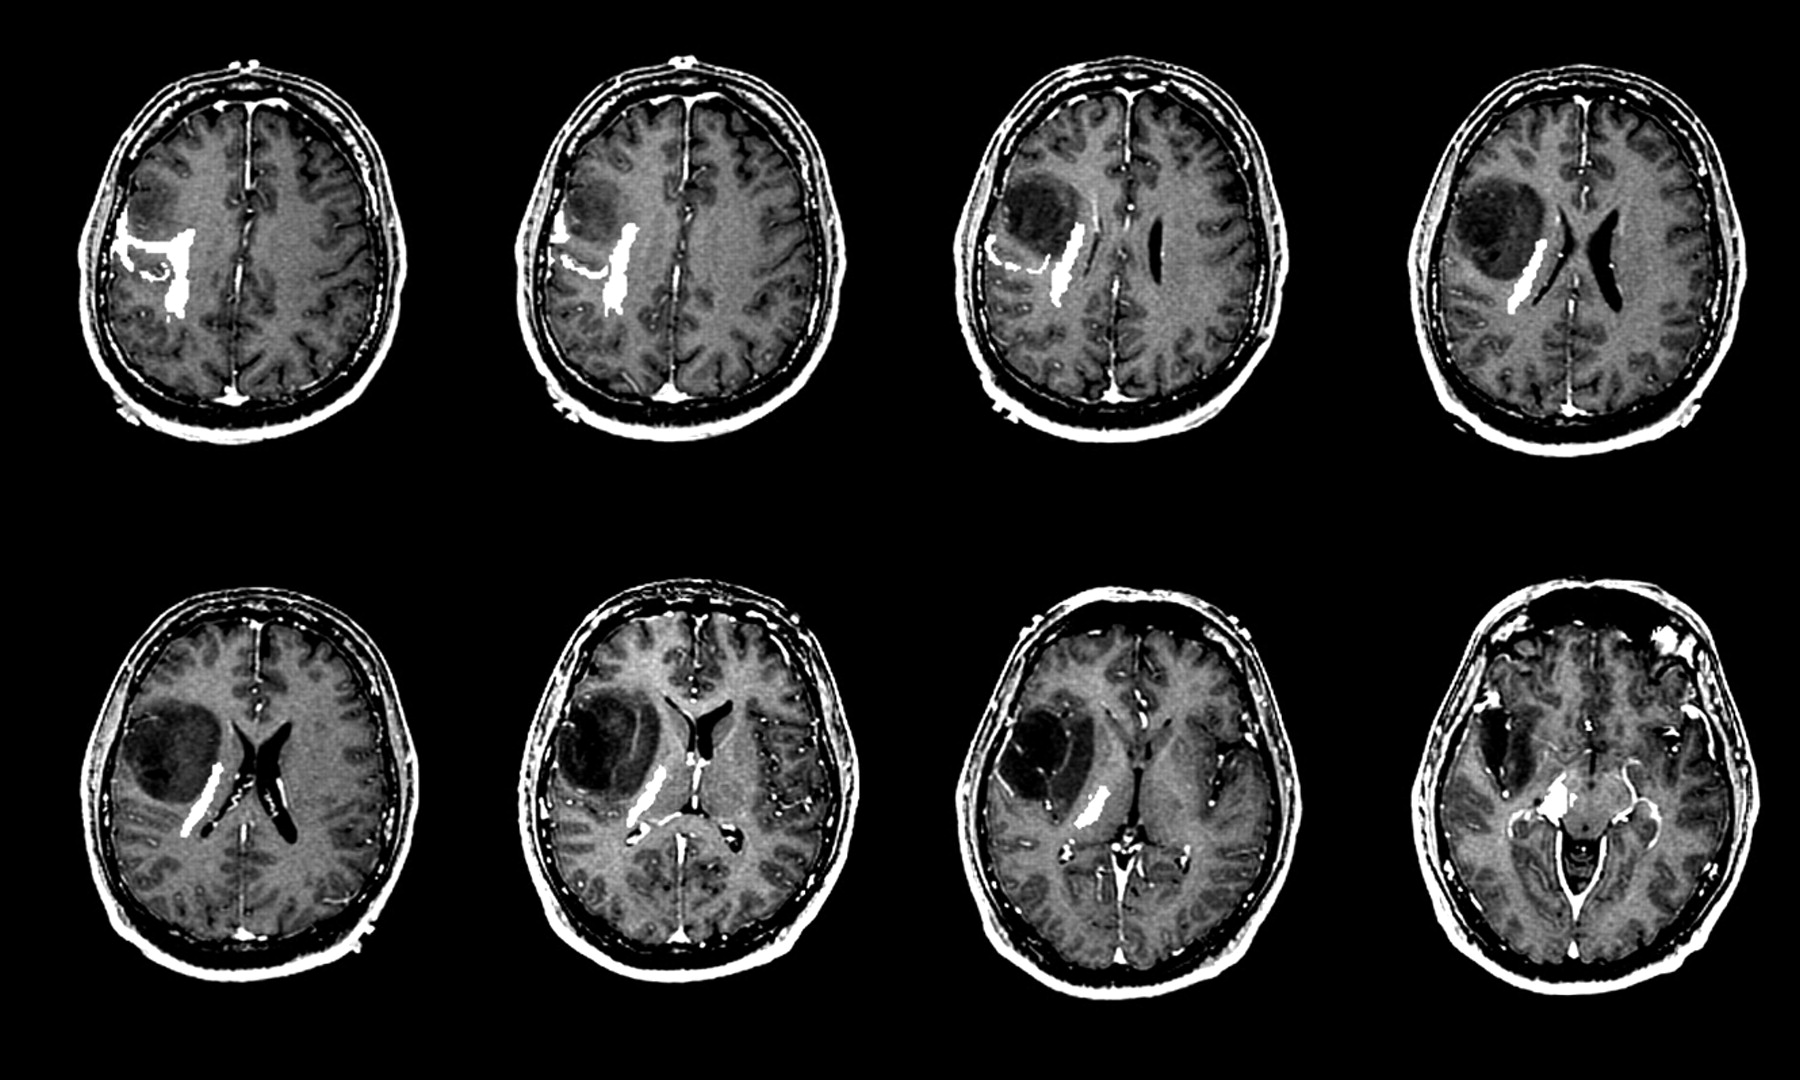

Pursuing a career in medical imaging is a commendable choice, and understanding the financial potential of this profession is often the first step for prospective students. If you are considering entering this specialized field, researching the MRI technician salary is essential for career planning. Magnetic Resonance Imaging (MRI) technologists play a critical role in the healthcare system, providing diagnostic images that help physicians detect, diagnose, and treat a wide array of medical conditions. Because this role requires specialized training, certification, and technical expertise, it is generally considered a lucrative profession within the allied health sector.